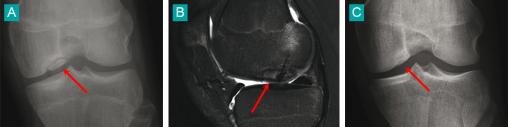

A. Première radio. B. Traité par vissage à l'aide de matériel résorbable. C. Le résultat radiographique à 2 ans de recul. Voir : P. Journeau, E. Polirzstok, F. Launay, D. Barbier. Lésions osseuses de sollicitation excessive chez l’enfant sportif. Rev Prat 2015;65(8);1084-90.